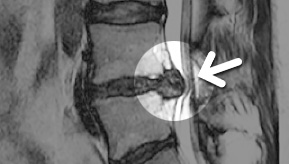

MRI

ϰ ڻ ͼ ̶ ؿ.

ü Ƶ ̰ ȣ µ

㸮 , ٸ ʹ

, Ƹ, ߰ ļ

Ȱ ް

MRI ġ